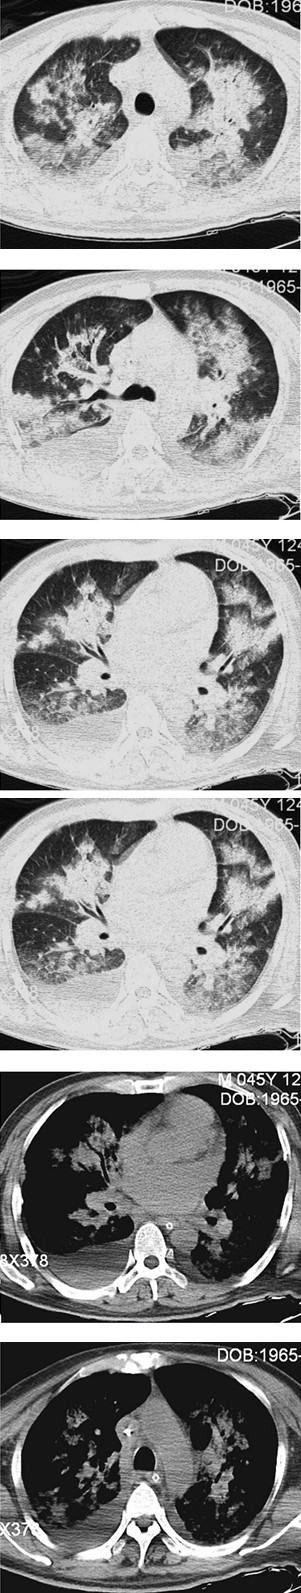

辅助检查:复查胸部X线、CT提示双肺广泛感染伴双侧胸腔积液(图63-1、图63-2)。

图63-1 起病第19天(入笔者医院当天)胸片提示两肺广泛感染

图63-2 起病第20天(入笔者医院第2天)CT提示两肺感染、渗出病变,双侧胸腔积液